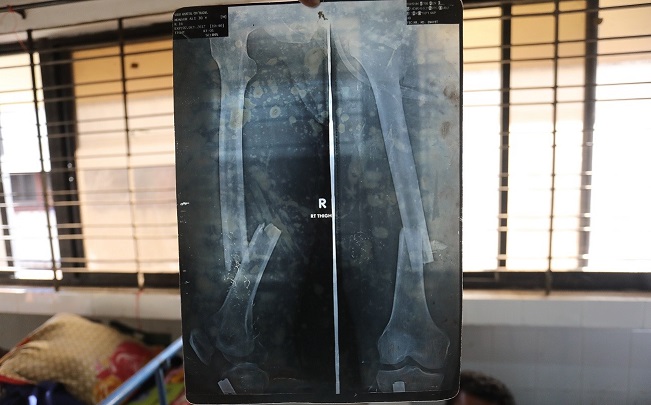

He went immediately to a hospital where little was done for him. An X-ray showed a broken bone. Korim still could not lift any weight with his left arm and felt very weak. He had a newborn child, who he couldn’t carry in that arm. He had persistent aching chest pain and fatigue.

PHR Medical Evaluation

Korim’s exam was consistent with his narrative. His weakness was obviously visible and represented a more than superficial injury to the limb’s bone, nerves, and muscles, which includes a rotator cuff tear.

Korim had an entry and exit bullet wound in the left upper back just over the superior scapula (shoulder bone). The entry wound is about 1.5 cm and circular. The exit wound is oval-shaped with the medial (middle) area appearing with a scab and an extended lateral oval area, consistent with a bullet injury. The scab area, according to the patient, is very itchy and he scratches it regularly. He had no history of bone or soft tissue infection or pus draining from the limb. The wound appeared clean, dry, and intact and was forming a small scab. He had no pain when examining the wound by the examiner’s hands or no tenderness to palpation. His scapula (shoulder bone) and clavicle (collar bone) appeared intact.

Korim had significantly limited range of motion and could not lift his left arm above his head and has limited posterior (backward) movement, a severe limitation that constitutes a disability (per WHO definitions).[96] The length of time since the initial injury, coupled with the lack of progress made over time, classifies this as a long-term, and likely permanent, disability.